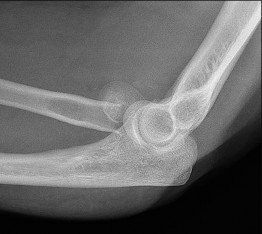

A 65-year-old male who underwent a cementless total hip arthroplasty (THA) 15 years ago presents with new-onset thigh pain. Radiographs reveal eccentric positioning of the femoral head within the acetabular shell and large retroacetabular and proximal femoral radiolucencies.

What is the primary biological mediator released by macrophages that directly stimulates osteoclastogenesis and is responsible for the observed bone loss?

Explanation

The radiograph demonstrates particle-induced osteolysis, secondary to polyethylene wear debris. When macrophages phagocytose these particles, they release pro-inflammatory cytokines, most notably TNF-a, IL-1, and IL-6. These cytokines stimulate the RANK/RANKL pathway, activating osteoclasts and leading to significant periprosthetic bone loss. IL-10 and IL-4 are anti-inflammatory cytokines, while IFN-y actually inhibits osteoclastogenesis.